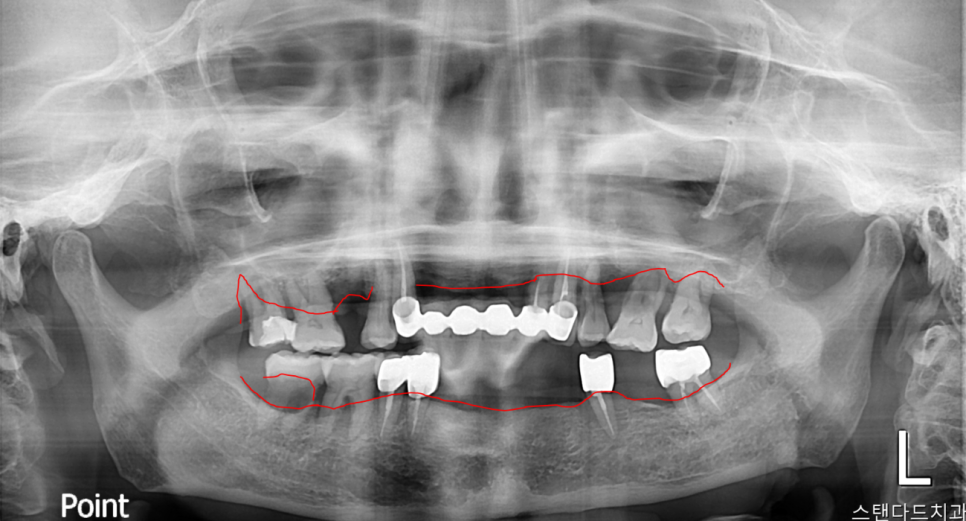

초진사진

촬영:2024년1월9일

방사선 사진으로 확인해 본 결과

예상했던 대로 상악 치아 전체적으로 치주염으로 인한 치조골 소실이 심하고

하악의 경우 다수의 치아의 상실과 우식 그리고 염증 소견이 보이는

심각한 치주염 상태입니다.

남아있는 모든 치아들이 잇몸에 매달려있는 상태(Floating tooth, 부유치)로

흔들리고 빠지기 직전이었습니다.